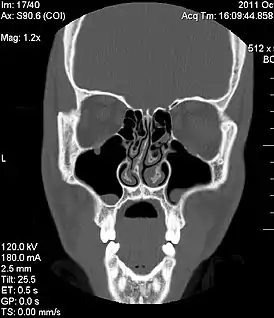

![]() Изображение компьютерной томографии, показывающее врожденное отклонение носовой перегородки | |